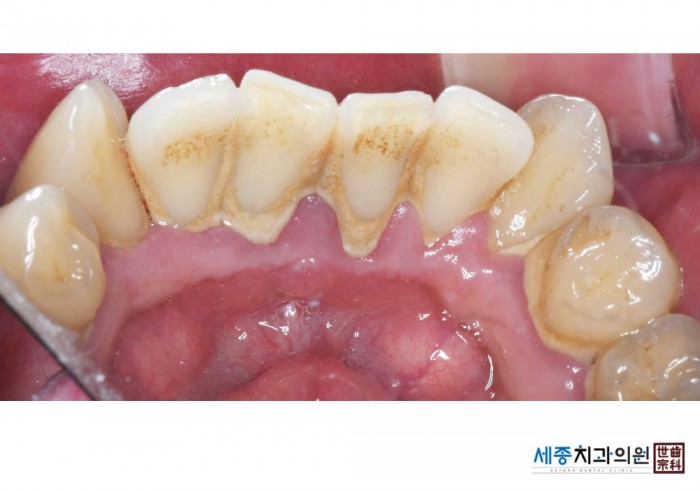

[스케일링] 치주질환 예방 스케일링

치료전 : 2025-09-10

가글마취&저주파 스켈러를 사용한 착색제거 스케일링